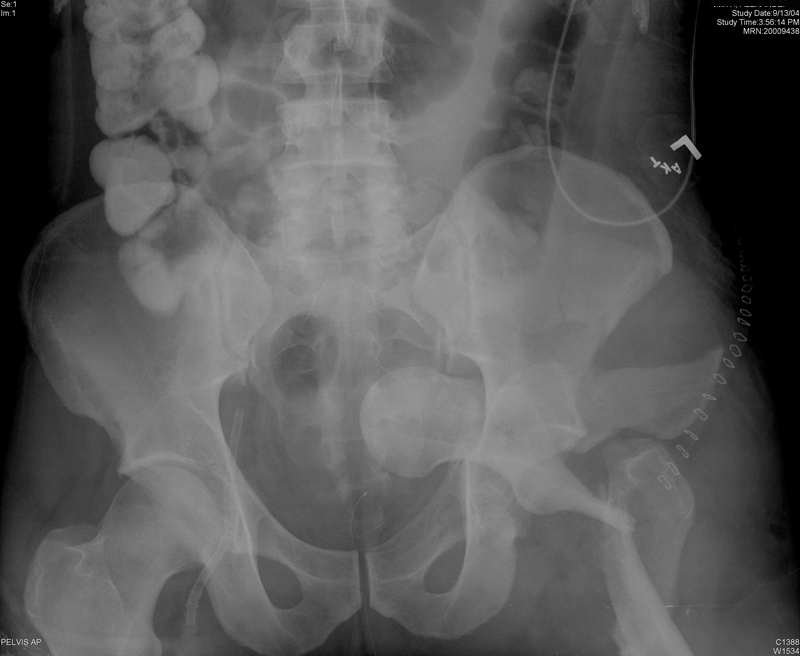

Intrapelvic farcture dislocation of the hip

Anyone ever seen one like this before? Any suggestions on how to get that thing out of there,because I tried and couldn't

-got called in to the OR by a colleague with the patient already on the fracture table and 2 big incisions (lateral and iliac crest) already made. Gave up after an hour or two and will try again if I can figure the solution.

Yes. We used a Watson-Jones exposure, spread the acetabular fracture with a laminar spreader, and used a Schanz pin to remove the proximal femoral fragment, then fixed it, and later fixed the acetabular fracture.

I have had one very similar. I placed him lateral decubitus, did a posterior approach, and did similar to what Chip described. The posterior approach allowed me to fix what appears to be a transverse acetabular fracture. The femoral neck can be fixated from that approach with multiple screws, although there may be more there than "just" a neck fx. The patient later required hemiarthroplasty for total head osteonecrosis.